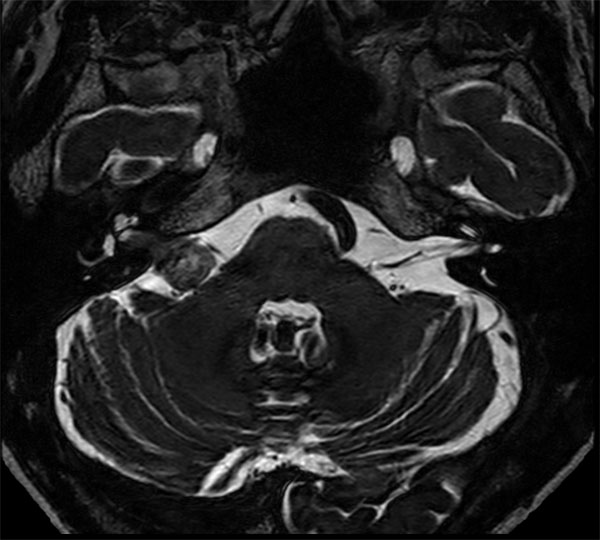

IAC – Acoustic Neuroma

Decreasing hearing of the right side. Buzzing and beating sensation in the right ear. Sometimes pain. Request for MRI of the inner ear without and with contrast agent.